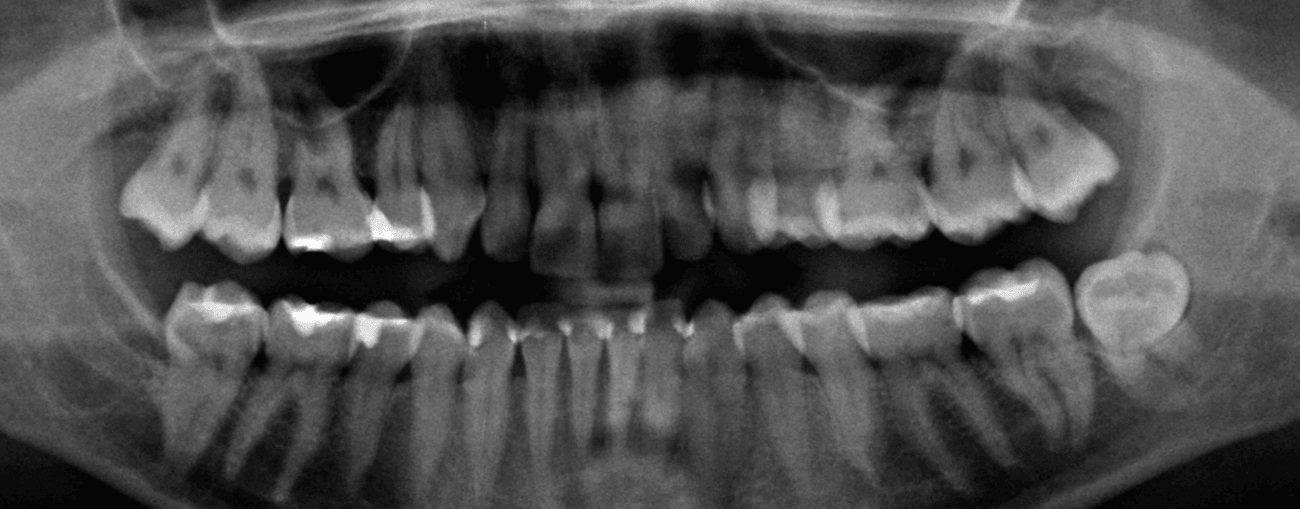

Paciente de 76 anos do sexo masculino

Motivo da consulta: Paciente desdentado total, procurava colocar dentes.

Plano de tratamento: Colocação de 4 implantes superiores e 2 implantes inferiores. Confeção de uma barra superior e colocação de 2 locators® na parte inferior. Confeção de uma prótese superior e outra inferior removível, com encaixes na barra e locators®.

A escolha deste plano de tratamento deve-se ao facto de o paciente querer uma solução total, mas não completamente fixa, uma vez que não tinha muita destreza manual para higienizar uma prótese fixa. Desta forma, conseguiu uma solução bastante retentiva (devido aos encaixes) mas que consegue remover para uma higienização correta.